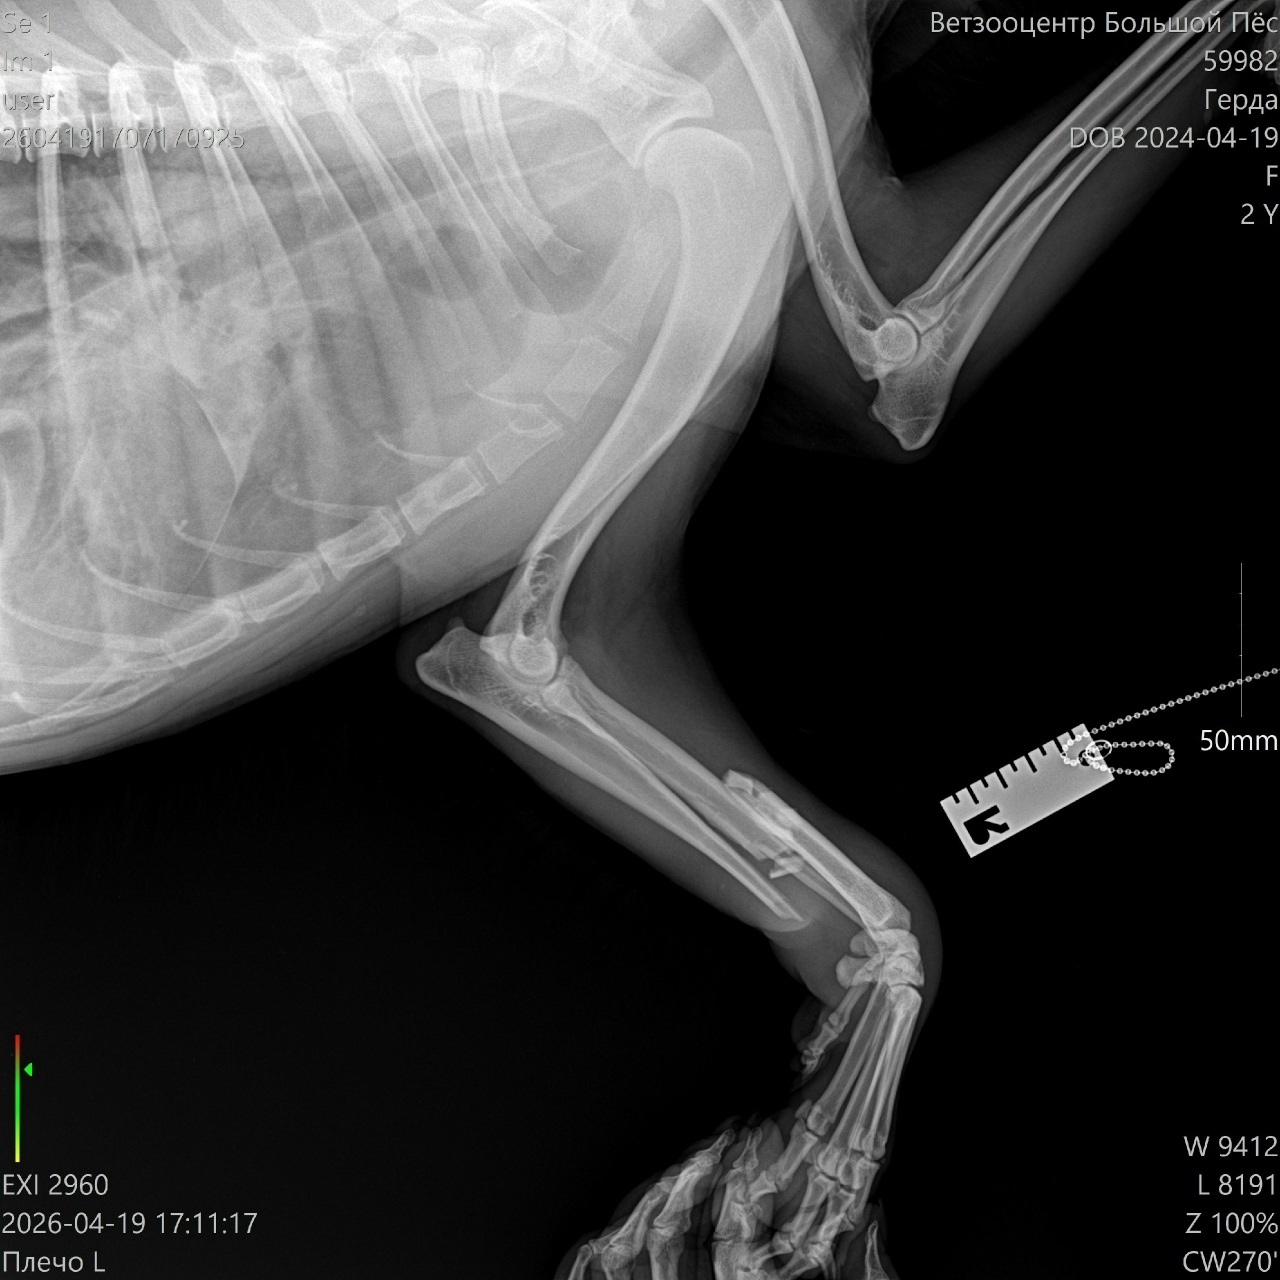

19 апреля была найдена сбитая собака в ошейнике с именем Римма, больше никакой информации. Ей сделали рентген - сложный перелом передней лапы. Собака крупная, 30кг. Находится временно в одном из СНТ. На посты о ней никто не откликнулся, хозяевам она видимо не нужна.

Собаку готовы принять в клинике "Ксоло" 23 апреля доктор Панков, либо в клинике "Юна", но нужны предварительно анализы, которых нет. По стоимости операция 50000 плюс стационар от 3500 до 6000 в сутки. Человек, приютивший на время собаку не располагает возможностями по ее содержанию и оплате. Есть возможность только привезти ее в Москву в клинику.